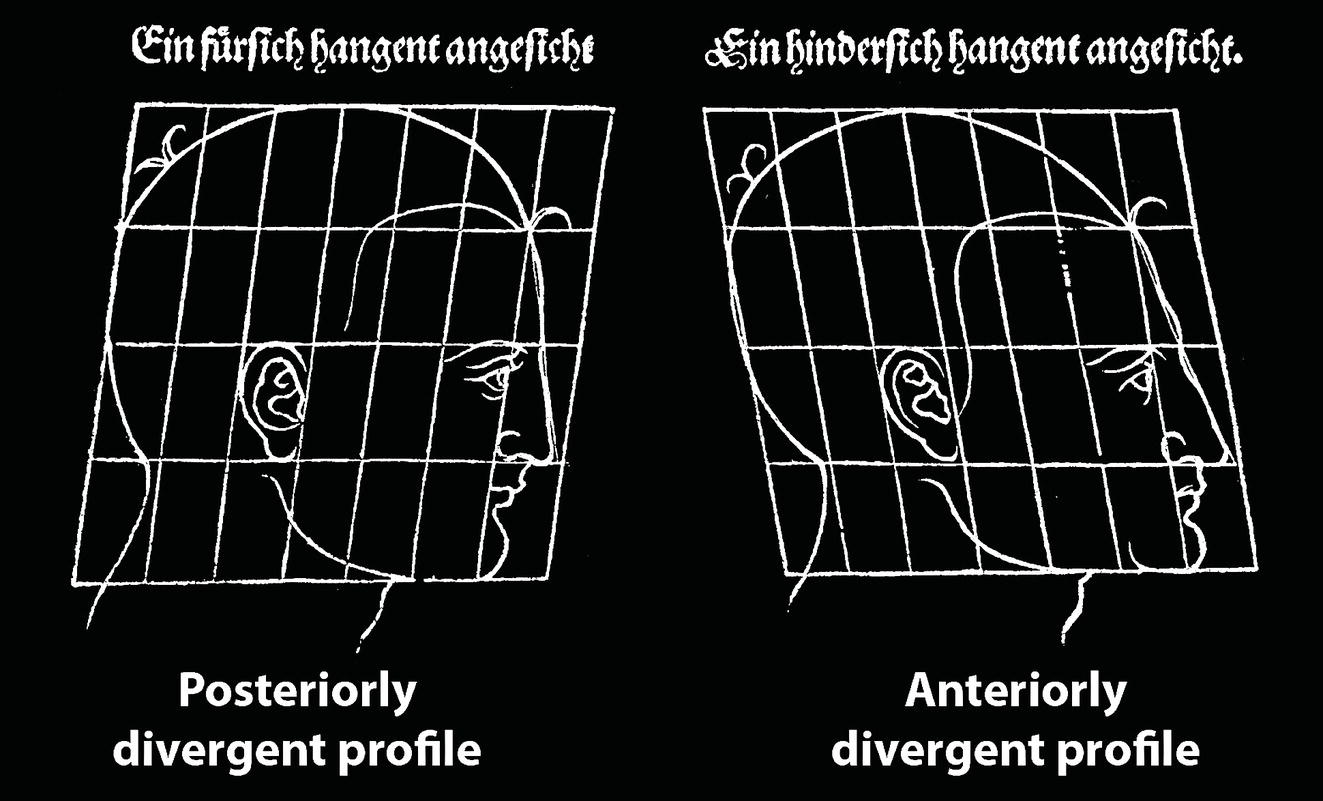

‘It is the common wonder of all men, how among so many millions of faces, there should be none alike’. Sir Thomas Browne (1605–82), English physician and writer, Religio Medici (1643)1 Individual variability is a fundamental principle in human biology. One of the most variable and distinguishable parts of the human body is the craniofacial complex. Clinicians will often compare a patient’s craniofacial measurements and proportions to the so‐called population norms (normative values) or even to classical ideals. However, Simon (1926) stated: ‘all we ever find are variations; an exact, ideal normal does not exist, cannot exist. And this is our enigma; in theory we will never find the normal, in practice we forever feel its need and apply it constantly’.2 The use of population norms may be logically enhanced by evaluating normal ranges of variability. Therefore, clinicians must have a thorough understanding of the normal ranges of variability in every aspect of craniofacial form, depending on age, sex and ethnic variability. Developmental disorders, as well as traumatic injuries and pathological conditions, may lead to deformities of the head and the face. Therefore, clinicians need to have a thorough understanding of the normal anatomy and morphological range of variation of the craniofacial complex in both males and females of different ages and ethnic groups, to act as guidelines when treatment planning the restoration of normal craniofacial proportions. Classifications that are useful for descriptive purposes include: A proportion index provides a numerical expression of the proportionality of a region of the craniofacial complex. The use of proportion indices dates back through the history of craniometry, particularly in the late nineteenth century. Linear (chord) or surface (arc) distances of the skull were measured between a variety of defined craniofacial landmarks; with any two measurements, the smaller was expressed as a percentage of the larger in order to provide a proportion index value. These could be used to provide an indication of skull shape. Figure 8.1 Determination of the normality or abnormality of any craniofacial measurement (or proportion index value) obtained from patients may be evaluated by comparison with the normative values obtained from a normal (average representative) population sample. The normal range of measurements is provided by the mean ±2 standard deviations (SD). The shape of the normal distribution curve shown is determined by the population standard deviation. Craniofacial parameters with small SDs have narrow, taller curves and those with large SDs have broader, flatter curves. Approximately 68% of all values fall within the range of ±1 SD from the mean and 95% within the range of ±2 SD from the mean. The normal range of variability for any craniofacial parameter is taken as being equal to the mean ±2 SDs. Greater differences may be perceived as deformities of gradually increasing severity. The leading researcher in the field of craniofacial anthropometry from the mid‐1960s to the early 2000s was Leslie Farkas, from the University of Toronto. Farkas et al. collected a large quantity of highly relevant anthropometric data between 1968 and 1984, from 2564 individuals.3 These data were used to provide 166 individual facial ratios, presented as proportion indices. In the creation of an index, the smaller measurement is multiplied by 100 (numerator) and divided by the larger measurement (denominator). Thus, a proportion index involves two linear craniofacial anthropometric measurements, with the smaller being expressed as a percentage of the larger. Proportion indices permit objective, quantitative assessment of facial morphology and proportions. Farkas3 identified two basic categories of proportion indices: Each proportion index will have a mean index value and a range of variation for a given population group, based on age, sex and ethnicity. The standard deviation (SD) determines the normal (average) range of variability of an index, from 2 SD below to 2 SD above the mean. Index values within this normal range are regarded as variations of normal proportions.4 Measurements within ±1 SD of the mean are regarded as optimal. The relationship between two measurements is disproportionate if the proportion index value is outside the normal range (Figure 8.1).4 For a number of facial parameters, single morphological measurements or proportion index values may have a large SD and, therefore, wide normal ranges of variation; as such, only measurements or proportion index values which differ considerably from the mean of the population will be perceived as deformities. Conversely, other facial parameters may have very small normal ranges of variability, in which case even a small difference from the mean may be perceived as a deformity. The cephalic index (index cephalicus) is a numerical expression of the ratio between the head width (biparietal diameter) and head length (fronto‐occipital diameter) of a living person. The cephalic index (CI) is calculated by the formula (Figure 8.2): Figure 8.2 Cephalic index. Where: The cephalic index is used in anthropometry to classify head types as (Table 8.1; Figure 8.3): Table 8.1 Classification of anatomical head types Index values according to Martin and Saller.5 Figure 8.3 Head types. The highest cephalic index values occur in the Chinese and the lowest values in African Americans. The larger index values of the Chinese differ significantly from those of whites or blacks (Table 8.2).6 A comparison of the cephalic index values of three ethnic groups was undertaken; North American Caucasians, northern European (German) and eastern European (Czech). The index values indicated a mesocephalic head type for both sexes of North American Caucasians and northern Europeans; and a brachycephalic (short‐wide) head type for the eastern Europeans.6 The head circumference is measured in the horizontal plane around the head, through the glabella and opisthocranion. However, it may be measured across ophyron (the point ‘On’, in the mid‐sagittal plane, of a line tangent to the upper limits of the eyebrows) rather than glabella in order to eliminate the effect of development of the frontal sinuses and superior orbital rims on head circumference.5,7 African Americans have the largest and the Chinese have the smallest head circumference for both sexes. The head circumference is slightly larger for blacks than for whites for both sexes.6 The initial step in facial analysis involves the examination of the face in frontal view in order to assess the overall facial shape. The variety of facial shapes is almost limitless. However, a simple assessment will allow an overall categorization of the basic facial shape. The basic facial shape in frontal view may be any combination of the following: Table 8.2 Cephalic index of three ethnic groups Data modified from Farkas.6 SD = standard deviation. Table 8.3 Head circumference of three ethnic groups Data modified from Farkas.6 SD, standard deviation. Figure 8.4 Facial height‐to‐width ratios. Variations in facial height and width result in an innumerable variety of the three basic facial shapes (round, square and triangular). For example, an oval facial type is a combination of an overall round face combined with increased vertical facial height and/or reduced facial width. The relationship of vertical facial height to facial width is an important indicator of overall facial shape. There are three methods of evaluating the vertical facial height‐to‐width proportion. These may be presented as proportions, percentages or indices: The facial index (index facialis or index of the morphological face height) is a numerical expression of the ratio between the facial height (nasion to menton) and the bizygomatic facial width (zygion to zygion) of a living person. The facial index (FI) is calculated by the formula: Where: The facial index is used in anthropometry to classify faces as (Table 8.4; Figure 8.6): Figure 8.5 Facial types according to Albrecht Dürer. (Modified from Dürer, 15288.) Figure 8.6 Facial types. Table 8.4 Classification of anatomical face types Index values: male according to Garson, 1885;9 and female according to Martin and Saller, 1957.5 The term facial divergence was introduced by the orthodontist‐anthropologist Milo Hellman,10 although the concept had been described by Albrecht Dürer (1528) (Figure 8.7).8 It is essentially a description of the slope or inclination of the face in the sagittal plane (Figure 8.8). It is determined by the sagittal position of soft tissue pogonion (Pog’) and subnasale (Sn) relative to a vertical line dropped from glabella (G’), with the subject’s head in natural head position. The factor that discriminates and distinguishes facial divergence from profile convexity or concavity is the sagittal position of subnasale (Sn) relative to the G’‐Pog’ line. In order for the face to diverge anteriorly or posteriorly, yet not to exhibit signs of convexity or concavity, subnasale (Sn) must be on or nearly on the G’‐Pog’ line; i.e. the upper facial plane (UFP, G′‐Sn) and the lower facial plane (LFP, Sn‐Pog’) are in a straight line, but diverge anteriorly or posteriorly. Figure 8.7 Facial divergence according to Albrecht Dürer. (Modified from Dürer, 15288.) Figure 8.8 Facial divergence. Anthropometric data from North American Caucasian males and females with untreated Class I dental occlusions describing normal facial divergence and ranges of variability has been provided.11 Mean values of facial divergence are negative, with the faces being slightly posteriorly divergent. Anterior divergence does not occur until two standard deviations from the mean. Facial divergence is essentially an ethnic variation in facial profile form. With a straight profile, i.e. no excessive profile convexity or concavity, anterior or posterior facial divergence is compatible with a normal maxillo‐mandibular and dental occlusal relationship. Figure 8.9 Facial profile contour according to Albrecht Dürer. (Modified from Dürer, 15288.) Figure 8.10 Facial profile contours. The contour of the facial profile may be described as convex, straight or concave. This concept was described by Albrecht Dürer (1528) (Figure 8.9).8 With the patient in NHP, the overall contour of the facial profile may be described by the relationship between two lines: the upper facial plane (UFP), connecting glabella (G’) to subnasale (Sn), and the lower facial plane (LFP), connecting subnasale to soft tissue pogonion (Pog’). In a straight profile, these two lines form a nearly straight line. Such a facial profile is termed orthognathic (Greek orthos: correct or straight; gnathos: jaw). An angle between these two lines indicates facial profile convexity (pogonion behind relative to subnasale in the sagittal plane), or facial profile concavity (pogonion ahead relative to subnasale in the sagittal plane). A convex profile indicates a skeletal Class II jaw relationship (and/or sagittal chin deficiency), and a concave profile indicates a skeletal Class III jaw relationship (and/or sagittal chin excess). However, profile convexity or concavity does not of itself indicate whether the maxilla or mandible/chin is at fault (Figure 8.10). Legan and Burstone12 described the angle of facial convexity for the soft tissue profile. It is formed by the two intersecting lines, the UFP (G′‐Sn) and the LFP (Sn‐Pog′). The mean value is estimated to be 12° ± 4°. An increase in the angle in a clockwise direction is positive; anticlockwise is negative. A high positive value suggests facial profile convexity and a Class II skeletal jaw relationship; a smaller positive value, or a negative value, suggests facial profile concavity and a Class III skeletal jaw relationship. However, the value of this angle does not reveal whether the maxilla or mandible/chin is responsible for the sagittal jaw discrepancy. Figure 8.11 Angle of facial profile convexity (facial contour angle). Downs13 described the angle of convexity, formed by the intersection of line nasion to point A (NA) and line point A to pogonion (A‐Pog). Superior extension of the A‐Pog line forms an angle with the NA line; if behind the NA line, the angle is read as positive, indicating a Class II (convex) skeletal profile. A negative angle of convexity indicates a Class III (concave) skeletal profile. Downs provided a range of values from −8.5° to 10°, with a mean of 0°. Again, as with the facial contour angle, the angle of convexity does not determine the localization of the deformity to the maxilla or mandible/chin. An investigation was carried out with the objective of assessing how lower facial profile convexity influences perceived attractiveness. The lower facial profile of an idealized image was altered incrementally between 14° and −16°, creating a range of images which were evaluated by pretreatment orthognathic surgery patients, laypeople and clinicians. A straight profile was perceived as most attractive and greater degrees of convexity or concavity deemed progressively less attractive, but a range of 10° to −12° was deemed acceptable; beyond these values surgical correction was desired. Patients were most critical, and clinicians were more critical than laypeople.14 The facial angle indicates the relative sagittal prominence of soft tissue pogonion. It is formed by the intersection of the true horizontal plane (or Frankfort Horizontal plane) with a facial vertical plane (N′‐Pog’). The angle should be approximately 90°–92°. A greater angle indicates prominence of soft tissue pogonion; an angle less than 90° indicates retrusion of soft tissue pogonion. The soft tissue facial angle does not of itself determine the aetiology of the sagittal position of soft tissue pogonion, which may be due to one or a combination of: Consequently, the facial angle must be used in conjunction with other measurements and analyses. In addition, when constructing the facial vertical line (N’‐Pog’), if the sagittal position of nasion is not acceptable, it may be adjusted to a more ideal position. The alternative is to use soft tissue glabella (G’) rather than nasion. Downs13 described the facial angle as the inferior inside angle in which the facial line (N‐Pog) intersects the Frankfort Horizontal plane. Downs found a mean value of 88° with a range of 82°–95°. It indicates the relative sagittal position of the mandible/chin to the upper face. Figure 8.12 Facial angle. FH, Frankfort Horizontal plane; TrH, true horizontal plane. Figure 8.13 The relationship of the cranial base angle (saddle angle) and anterior cranial base length on the jaw relationship. The relationship of the anterior to the posterior cranial base is of particular importance in the diagnosis of facial profile contour. This relationship depends on the extent of growth at the sphenoethmoidal and spheno‐occipital synchondroses. The cranial base angle (or saddle angle) represents the orientation of the anterior cranial base (SN line) relative to the posterior cranial base (S‐Ba line).15 The average adult values (bearing in mind that there is negligible change in this angle after the age of six years) for the angle N‐S‐Ba are16: As such, the cranial base angle is an important determinant of craniofacial form, as it influences the sagittal position of the face relative to the neurocranium and the sagittal prominence of the mandible relative to the maxilla. A significantly increased cranial base angle contributes to a skeletal Class II jaw relationship, whereas a reduced cranial base angle contributes to a skeletal Class III jaw relationship. If basion is difficult to identify on a lateral cephalometric radiograph, articulare may be used instead, i.e. the posterior cranial base is drawn between sella and articulare. The average adult values for the angle N‐S‐Ar are16: The anterior cranial base length, measured from sella to nasion, may also influence the jaw relationship. For example, increased anterior cranial base length may lead to a Class II jaw relationship, with the maxilla ahead of the mandible in the sagittal plane, whereas reduced cranial base length may lead to a Class III jaw relationship, with the maxilla behind the mandible in the sagittal plane. The average adult values for the anterior cranial base length are16: Figure 8.14 Parasagittal profile contour. An additional and extremely important consideration is the description of the parasagittal profile (Figure 8.14). It is necessary to evaluate the sagittal relationships of the soft tissues from the infraorbital area to the paranasal area to the parasymphyseal area. For example, maxillary hypoplasia may lead to lack of bony support and flattening in the infraorbital region and paranasal hollowing; with a normal parasymphyseal area, this will lead to the appearance of a concave parasagittal profile. The directional pattern of facial growth has a significant effect on facial profile form. Deviations from the normal pattern of jaw growth may be in a predominantly vertical or horizontal direction. Alternative terms are hyperdivergent facial growth pattern (referring to the excessive divergence of the maxillary, occlusal and mandibular planes in relation to each other and to the anterior cranial base).17 Such a pattern of growth leads to a hyperdivergent facial type, alternatively termed a high angle patient (referring to the increased mandibular plane angle), long face deformity or long face syndrome.18 If the hyperdivergent growth is the primary aetiology to an anterior open bite, the terms skeletal open bite or apertognathia (Latin apertus: open; Greek gnathos: jaw) may be used.19,20 The maxilla rotates downward and backward (posterior vertical maxillary excess), as does the mandible during growth. This leads to reduced sagittal projection of the chin. Such a vertical facial growth pattern will tend to be associated with a posterior pattern of mandibular growth rotation. Figure 8.15 Hyperdivergent, ‘high angle’ facial type.

Facial type: frontal view (norma frontalis)

Facial shape

Facial height‐to‐width ratio/proportion (Figure 8.4)

Facial index